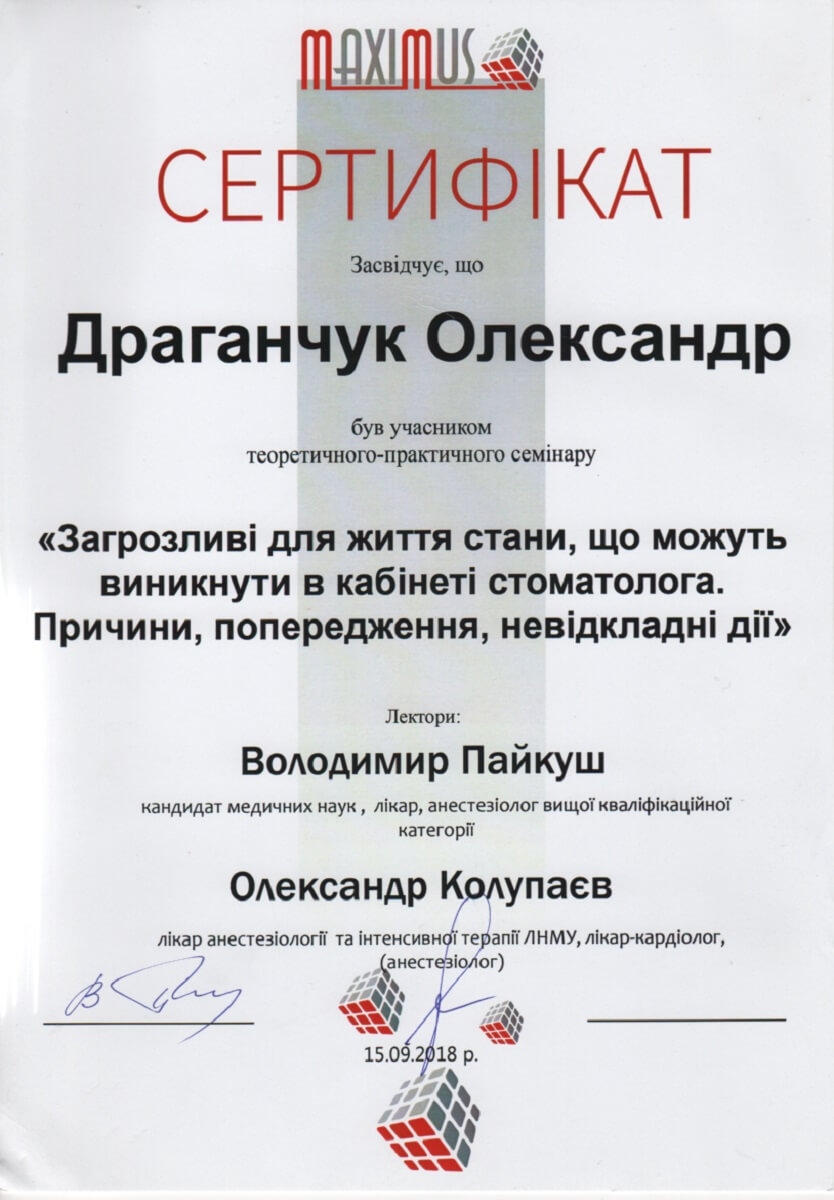

Ми пропонуємо тобі усю стоматологію в одній клініці. У нас ти отримаєш кваліфіковану стоматологічну допомогу: лікування і пломбування зубів та кореневих каналів, послуги з протезування, імплантації та стоматологічної хірургії. Космічна стоматологія Драганчука, це досвідчені фахівці, які навчались та стажувались в Берліні, Парижі, Вільнюсі та Будапешті, найсучасніші та найінноваційніші матеріали та обладнання.